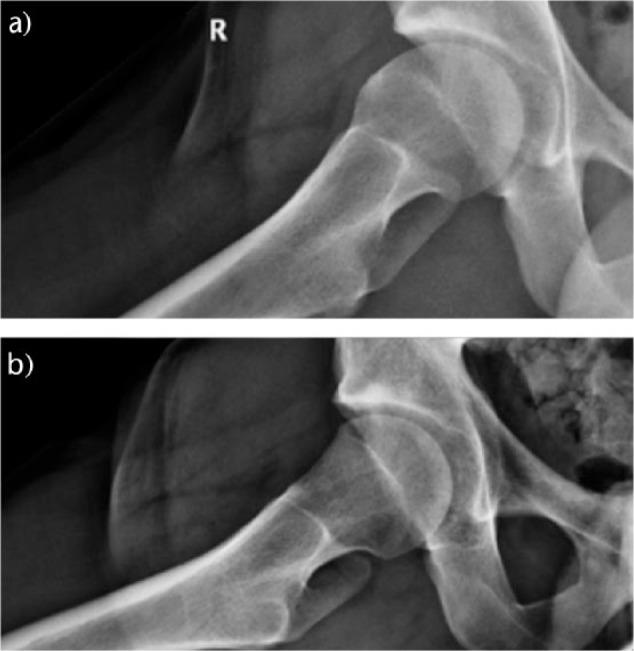

In this review, we bring to the attention of the reader three relatively unknown types of hip impingement. We explain the concept of low anterior inferior iliac spine (AIIS) impingement, also known as sub-spine impingement, ischio-femoral impingement (IFI) and pelvi-trochanteric impingement. For each type of impingement, we performed a search of relevant literature.We searched the PubMed, Medline (Ovid) and Embase databases from 1960 to March 2016. For each different type of impingement, a different search strategy was conducted.In total, 19 studies were included and described. No data analysis was performed since there was not much comparable data between studies.An overview of symptoms, clinical tests and possible surgical treatment options for the three different types of extra-articular impingement is provided.Several disorders around the hip can cause similar complaints. Therefore, we plead for a standardized classification. In young and athletic patients, in particular, there is much to gain if hip impingement is diagnosed early. Cite this article: 2018;3:30-38. DOI: 10.1302/2058-5241.3.160068.